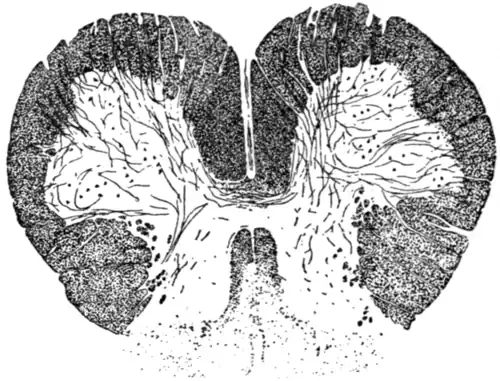

|

Fig. 8.—Diagram of section of the spinal cord in the upper cervical region, showing recent degeneration of the crossed pyramidal tract of the right side and direct pyramidal tract of the left side. The black dots indicate the degenerated fibres stained by the Marchi method. This degeneration is secondary to haemorrhage into the internal capsule of the left hemisphere, and it will be observed by the number of degenerated fibres that the greater bulk have crossed over to the right side of the spinal cord, thus agreeing with the fact that the paralysis is of the right half of the body. |